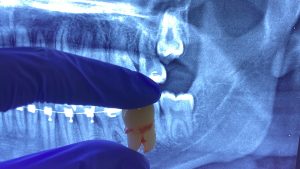

Gigi Bungsu: Dicabut atau Dibiarkan? Simak Panduan Lengkapnya

Banyak orang bertanya, “Jika gigi bungsu tidak terasa sakit, apakah tetap harus dicabut?” Jawabannya tidak selalu, namun seringkali gigi ini menjadi “bom waktu” bagi kesehatan mulut Anda.